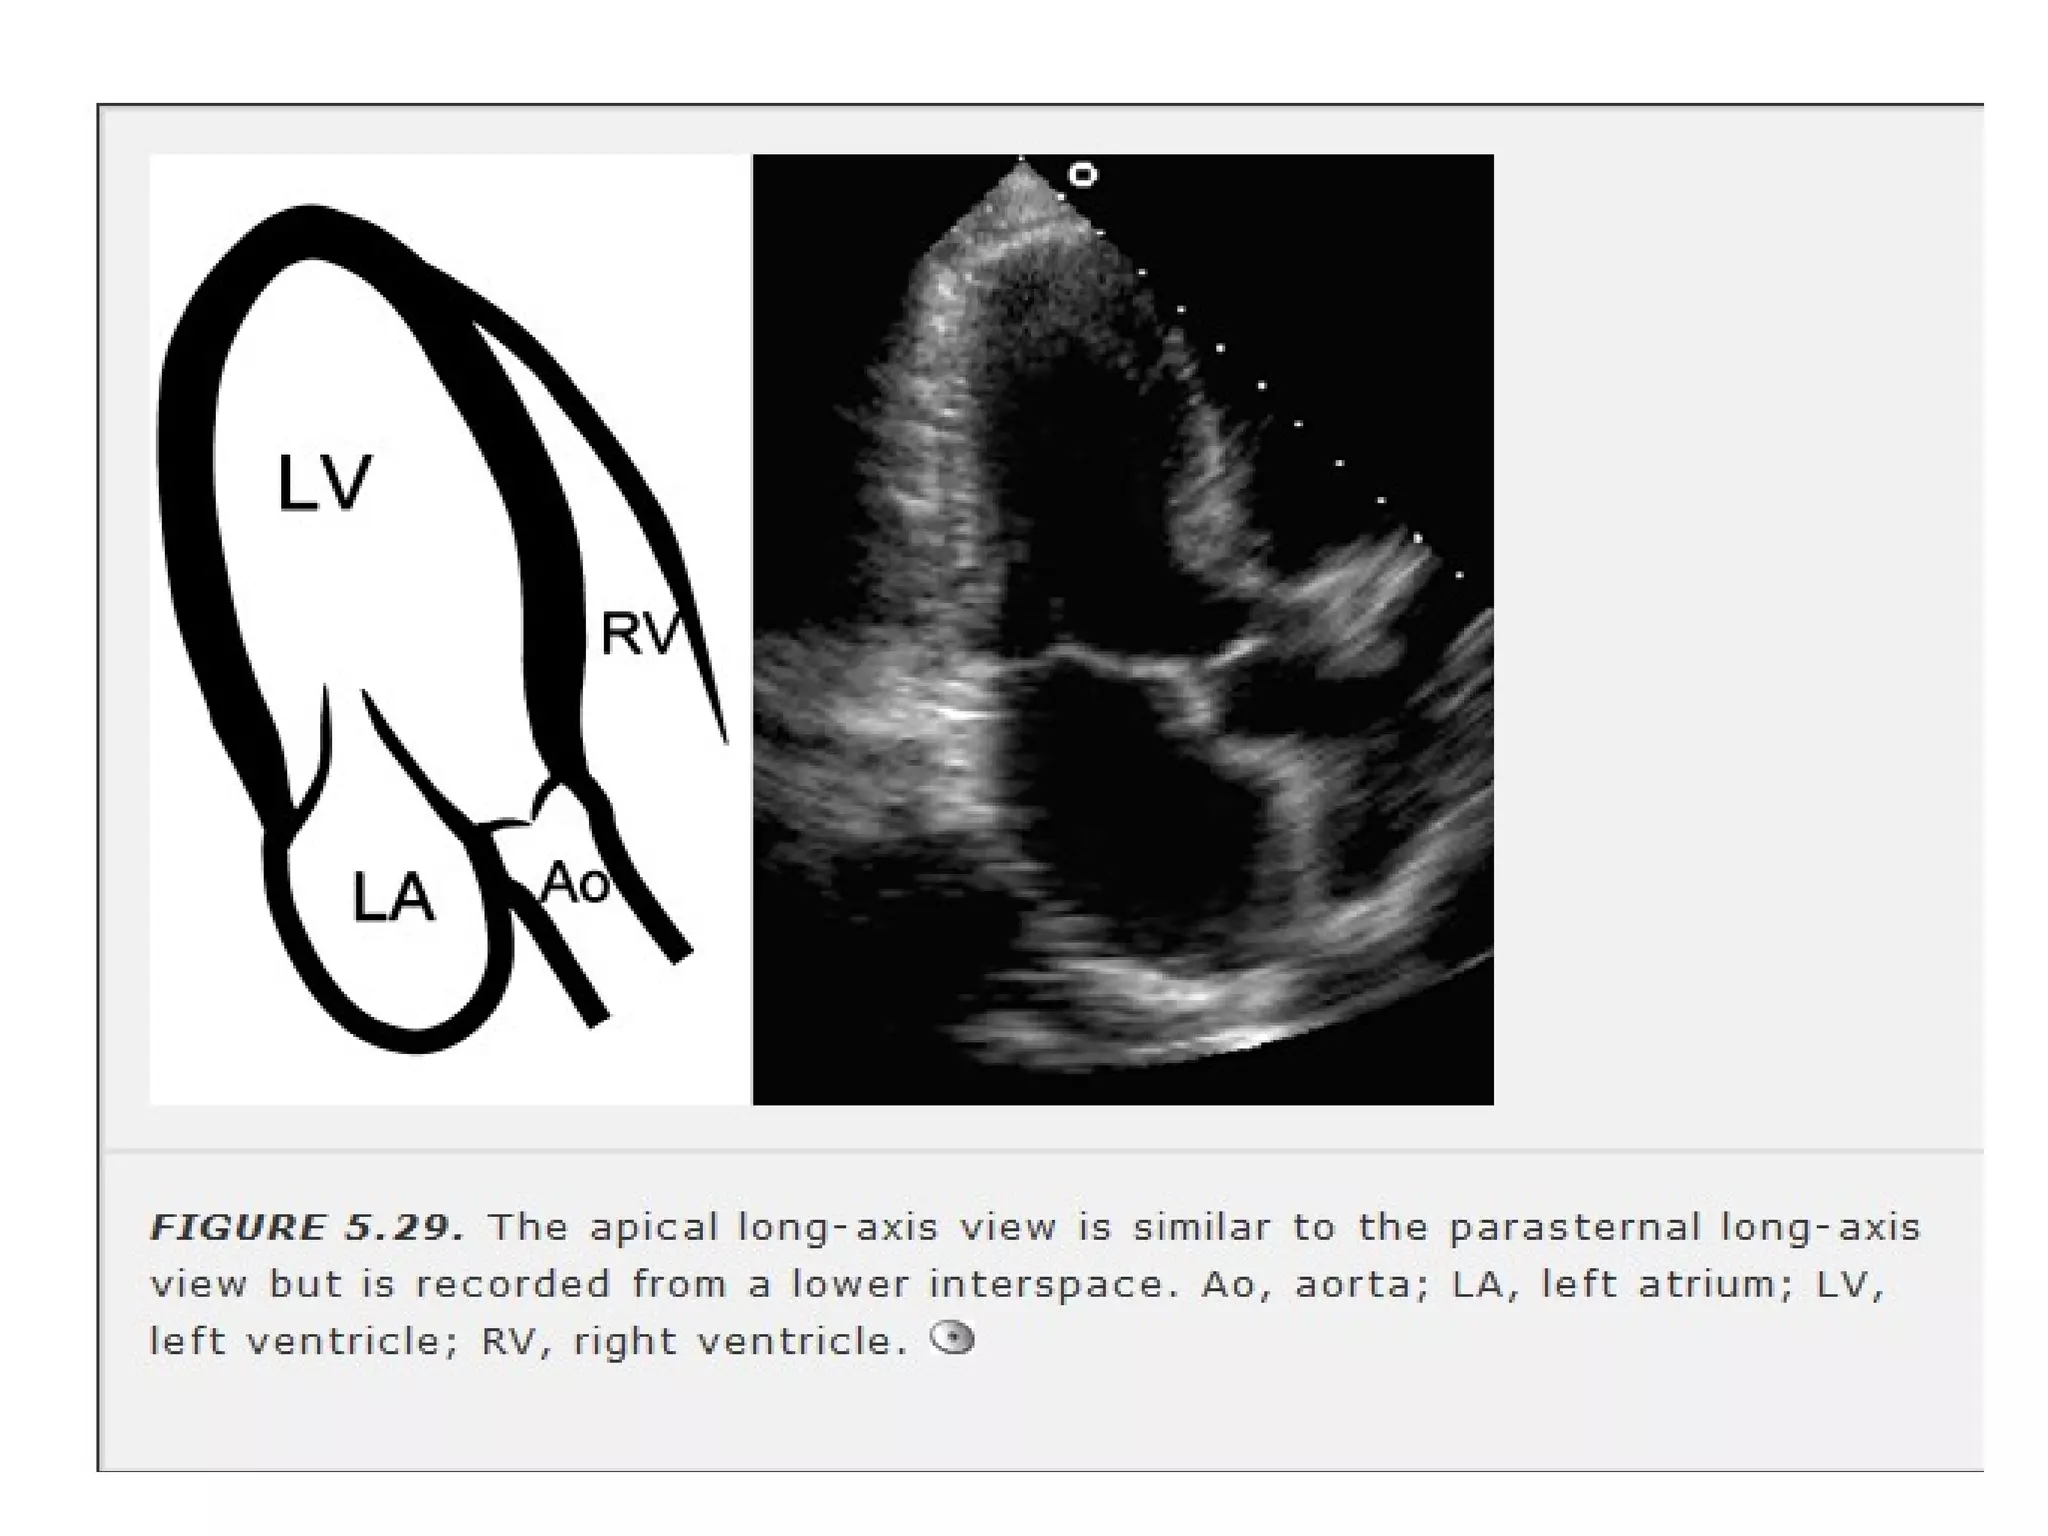

• Apical long axis view –transducer rotated

CW 60 similar to PLAX.

LV walls &

ultrasound beam are parallel.